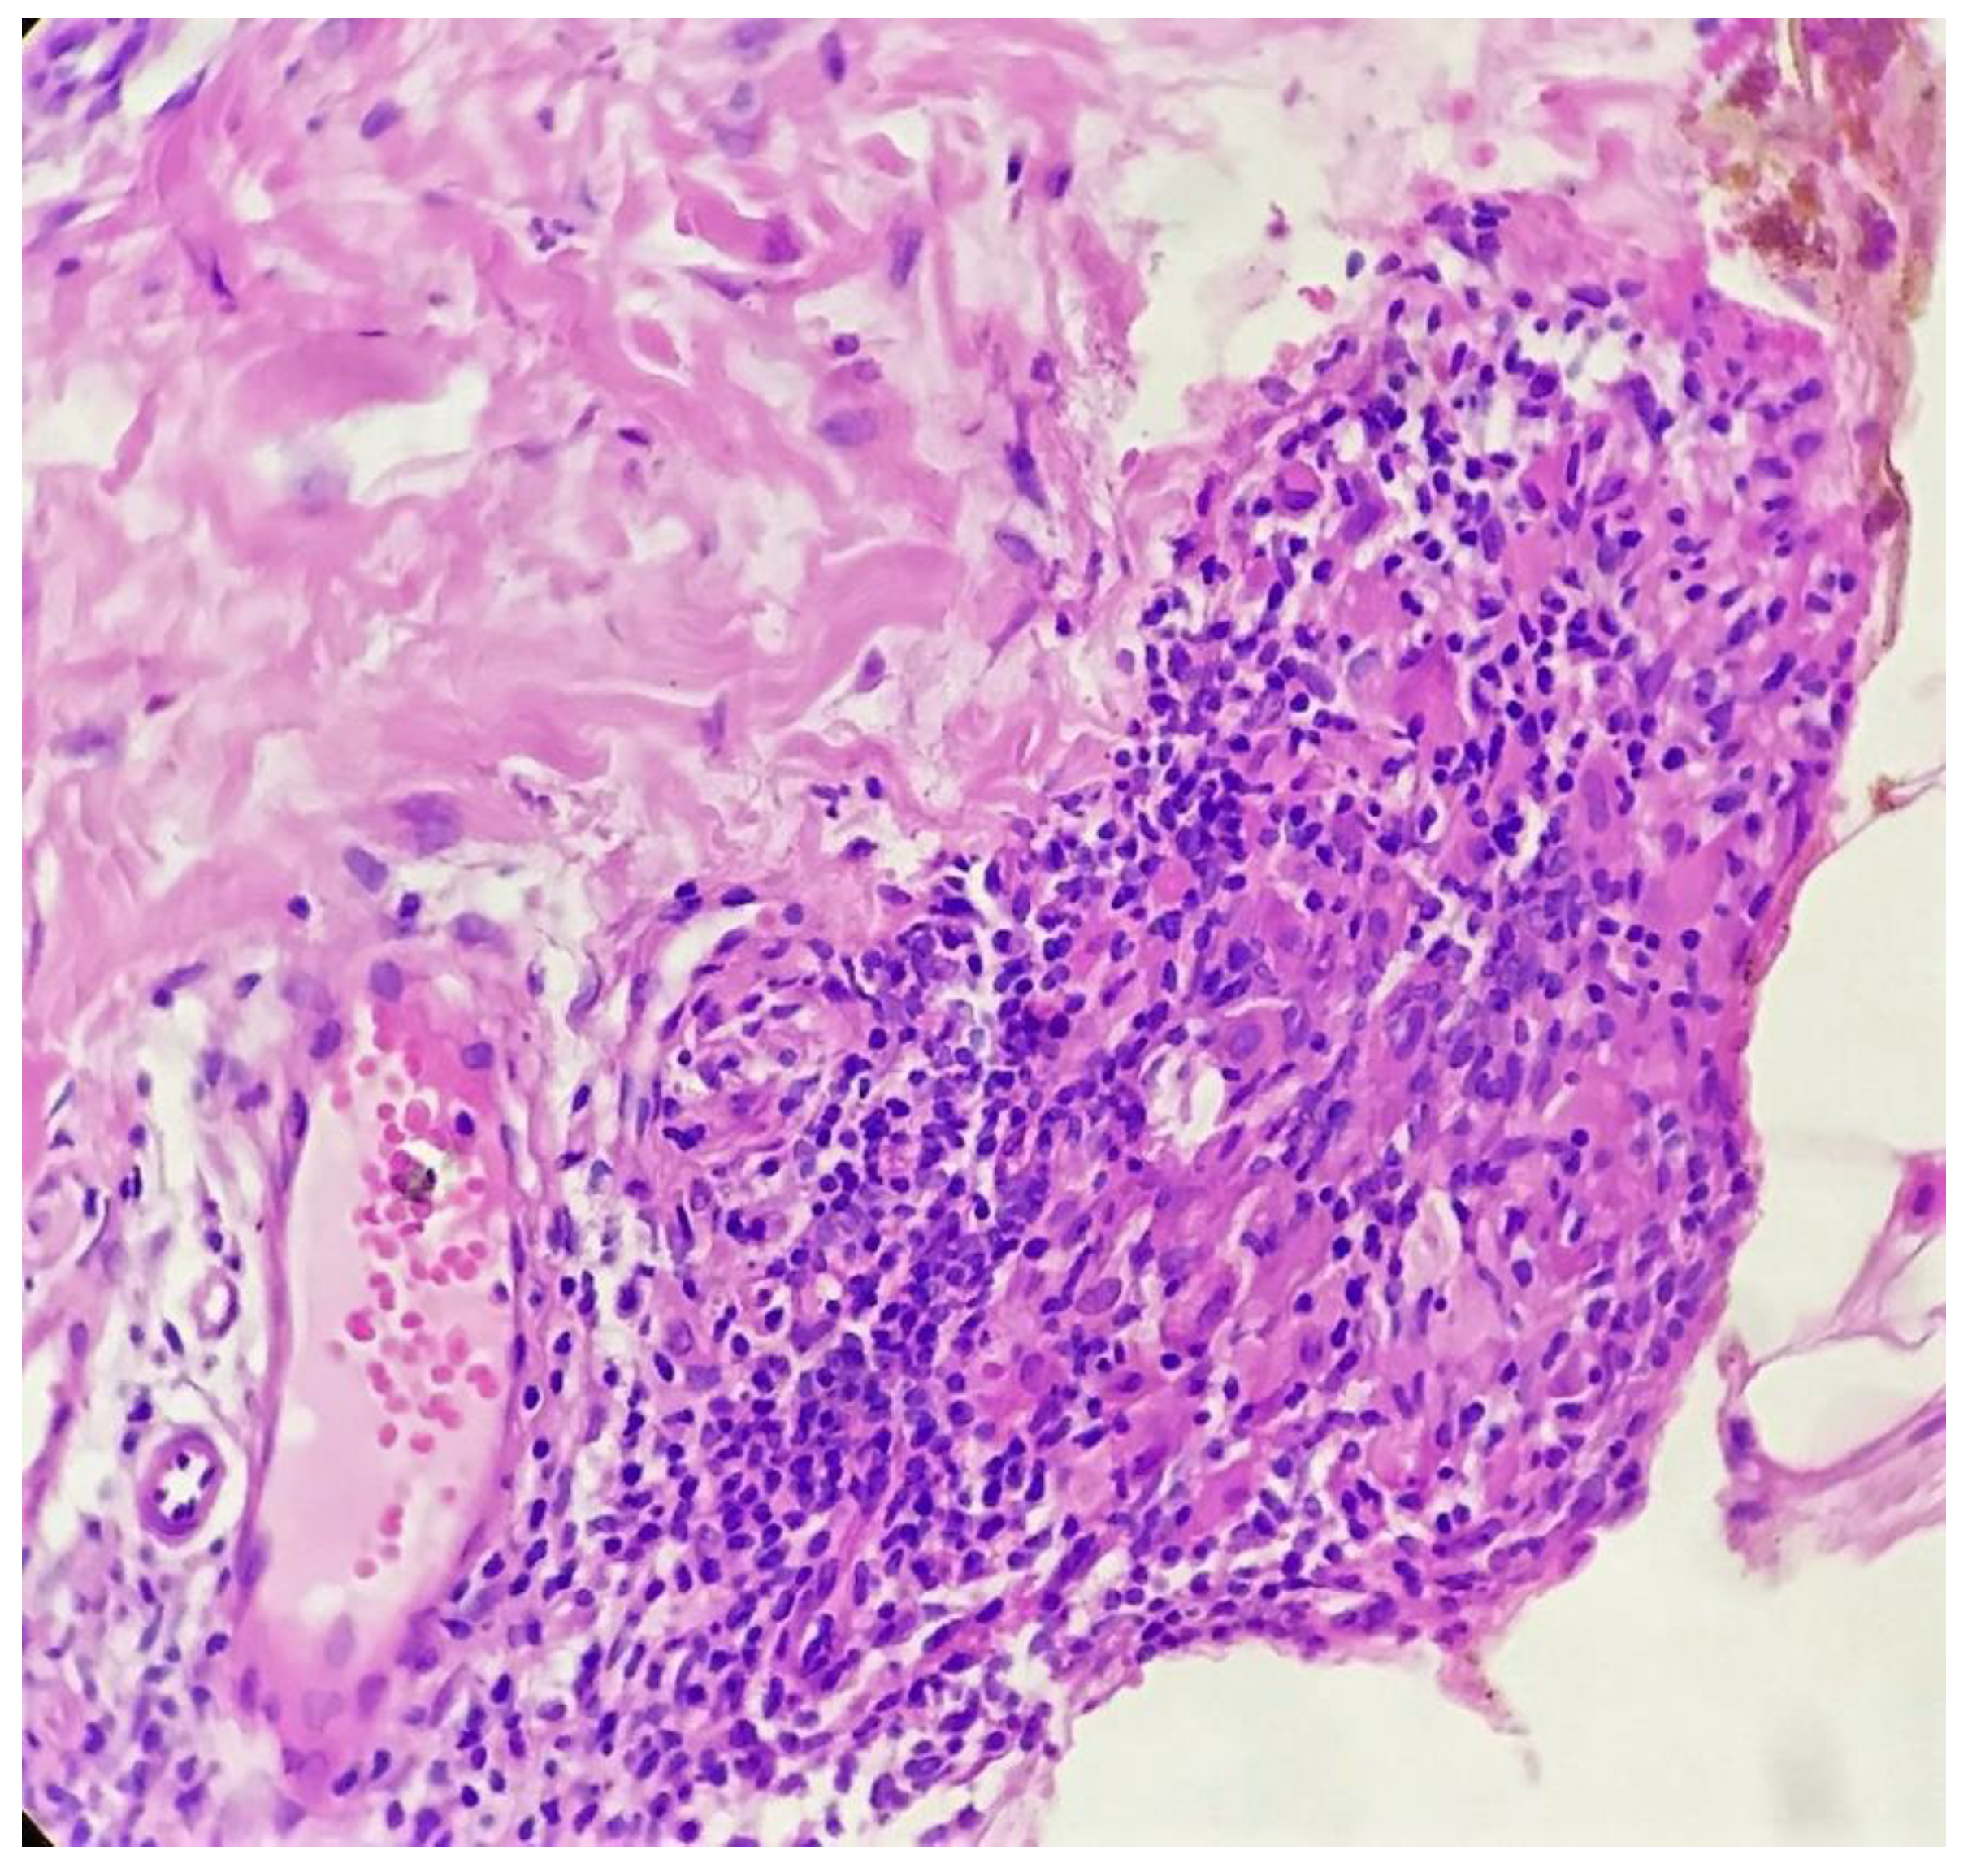

Biopsy showed a dense lichenoid and loose tuberculoid granulomatous infiltrate comprising of epithelioid cells, histiocytes and occasional Langhan’s giant cells, surrounded by lymphocytes and few plasma cells. The granuloma was seen abutting the overlying epidermis, which showed psoriasiform hyperplasia with mild to moderate spongiosis. A compact tuberculoid granuloma was also seen in the deep reticular dermis. Fibroplasia was also seen in the dermis (Figure 2, Figure 3, Figure 4 and Figure 5). The PAS-stained sections were negative for fungal organisms. Zeil–Neelsen stained sections did not reveal any acid-fast bacillus. Based on these features, a diagnosis of lupus vulgaris was favoured and further confirmation by culture study and PCR was advised.

Figure 5. Compact tuberculoid granuloma in deep dermis (H&E × 400).